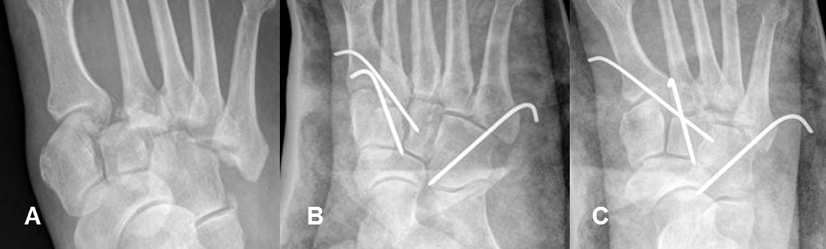

Fig 55 B. Luxofractura de Lisfranc.

A: Rx AP. Pérdida de las relaciones articulares entre todas las bases de los metatarsianos, las cuñas y el cuboides, por luxofractura de lisfranc.

B: Rx oblicua y C: Rx AP. Reducción de las luxaciones, con clavos de Steiman.